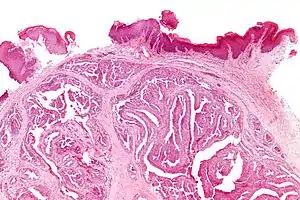

| Micrograph of a papillary hidradenoma with the characteristic papillary structures and epithelium with apocrine snouts. A fragmented overlying epidermis is seen at the top of the image. H&E stain. | |

A papillary hidradenoma, also hidradenoma papilliferum, is a sharply circumscribed nodule or benign tumor of the apocrine gland usually found on the labia majora or the interlabial folds. It is benign tissue (not cancerous) but is often confused clinically with carcinoma of the vulva because of its tendency to ulcerate.[1]